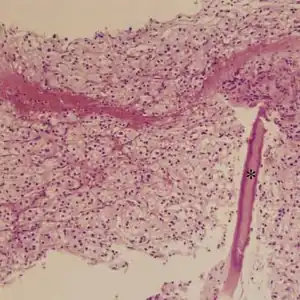

Metastatic alveolar soft part sarcoma of lumbar vertebrae

ASPS' histomorphologic features include an alveolar-like pattern at low magnification and the presence of large cells with abundant eosinophilic cytoplasm and eccentric nuclei. Calcifications are commonly present, as may be seen with slow-growing neoplasms.